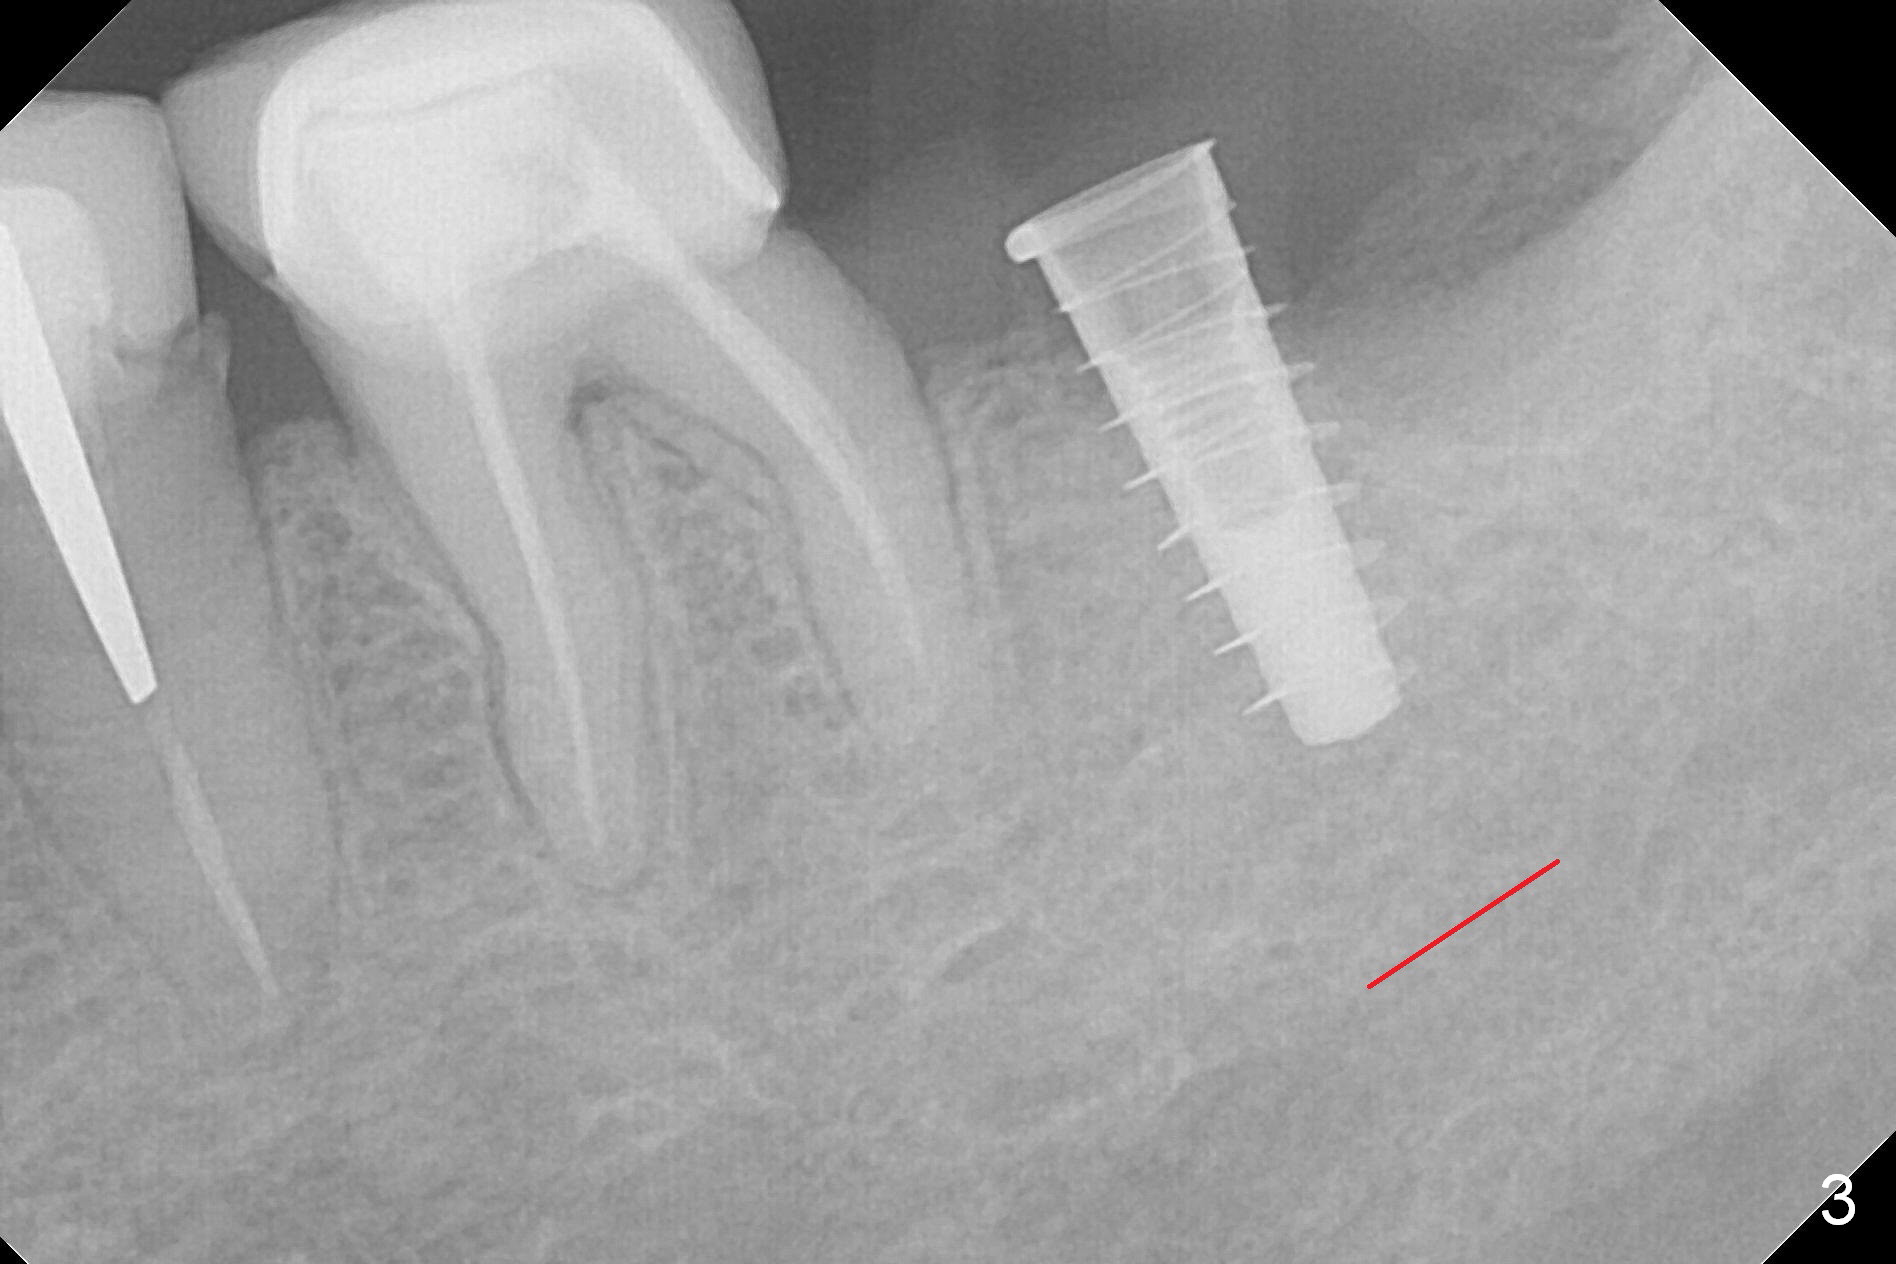

After 1.6 mm pilot drill (Fig.2) and 4.3 mm Magic Drill for 11 mm (gingival margin), a 4.5x11 mm dummy implant is placed with stability (Fig.3). Following Final Drill for 12/13 mm and 4.3 mm MD mesially, a 5x9 mm IBS implant is placed with 40 Ncm (Fig.4). Panoramic X-ray shows the placement is slightly supracrestal (Fig.5). In fact the implant is also placed slightly lingually. When the trajectory is changed, the implant loses stability. When a 5.5x9 mm implant is placed, no stability is achieved (Fig.6). After increase in osteotomy depth for 1-2 mm with MD 4.3 mm, the 5.5x9 mm implant barely obtains stability (~ 10 Ncm, Fig.7). Healing screw is placed. Osteogen plug is inserted in the distal portion of the socket; autogenous bone around the implant and Collagen plug to close the socket opening. Last suture and periodontal dressing are applied.